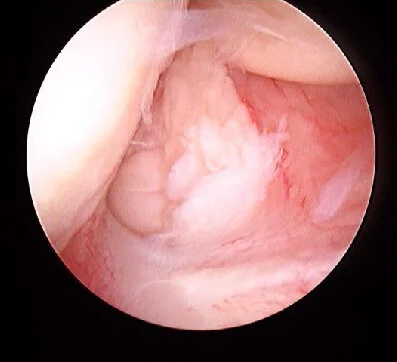

Figure 1: Wrist Extensor Origin and Capsular Tear